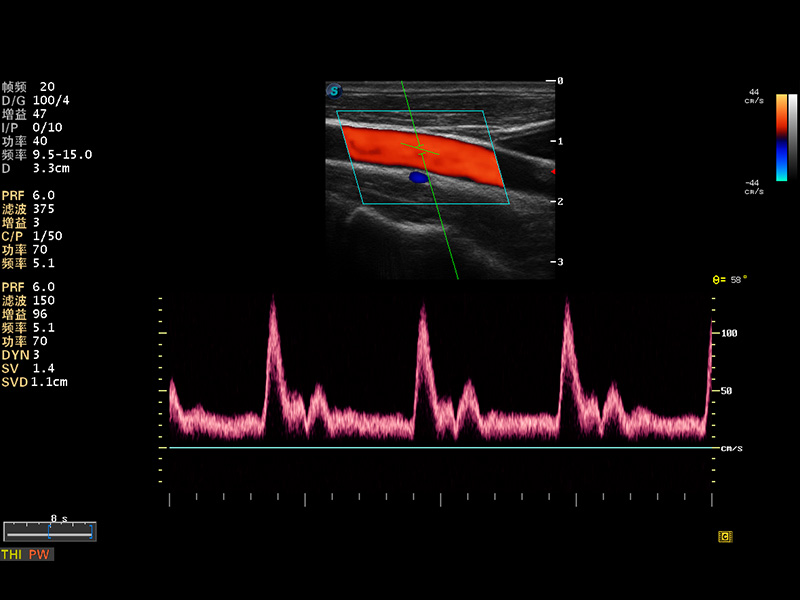

S8 EXP便携式彩色多普勒超声诊断仪是九州酷游研发的高端全身应用型便携彩超。高通道的VIS平台融合可视化(Visual)、智能化(Intelligent)和人性化(Smart)的特点,配以九州酷游自主研发生产的探头大家族,使您能够快速、准确的获得病人信息,提高工作效率的同时减轻疲劳。

μ-Scan微米成像

谐波成像